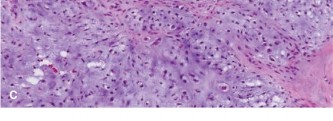

Which of the following histopathologic slides (Fig. 8–24A–D) is most consistent with osteosarcoma?

Figure 8–24 C–D

The correct answer is slide (D). Histologic examination of osteosarcoma reveals “lace-like” pink osteoid formed by malignant osteosarcoma cells. The degree of pleomorphism and atypia is considerable. Areas of necrosis with few viable cells (if any) are often seen.